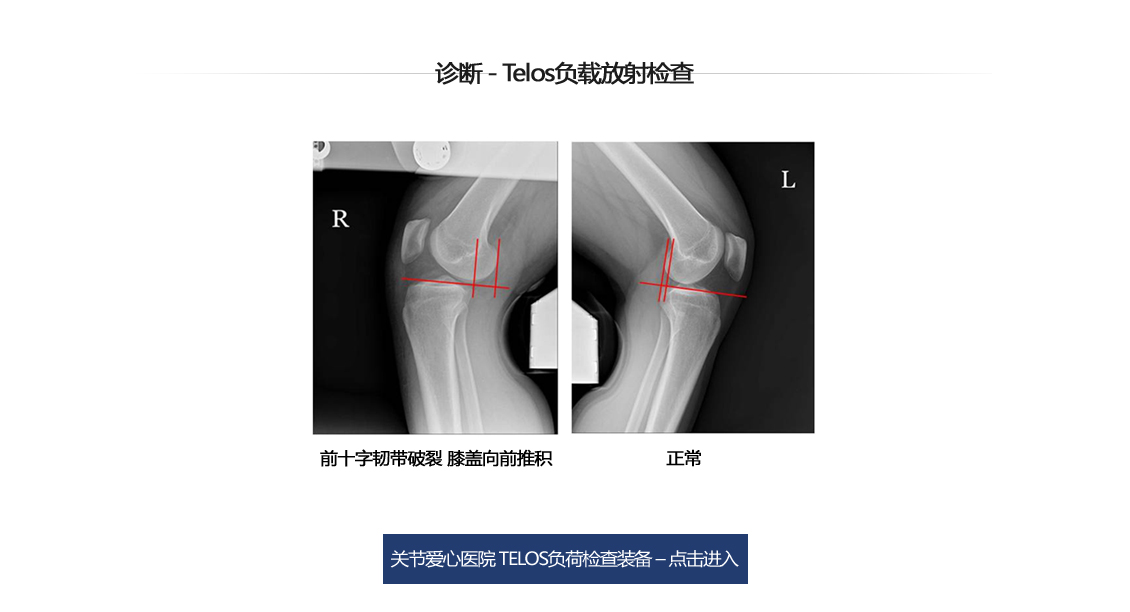

前十字交叉韧带断裂